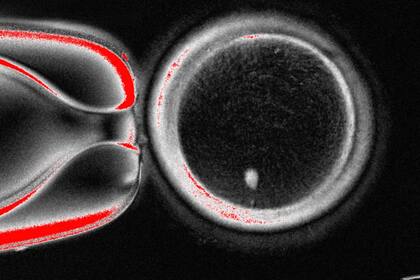

El equipo de OHSU extrajo el núcleo de una célula de óvulo humano y lo reemplazó con el núcleo de una célula de piel humana. Pero una célula de piel contiene dos conjuntos de cromosomas, y se supone que los óvulos y los espermatozoides deben contener solo un conjunto que se combine durante la fertilización. Por lo tanto, los investigadores indujeron a las células similares a óvulos a descartar cromosomas adicionales, inyectaron espermatozoides donados y activaron el desarrollo post-fertilización.

Aproximadamente el 9% duró seis días en platos de laboratorio, alcanzando la etapa de blastocisto del desarrollo temprano del embrión, antes de que se detuviera el experimento.